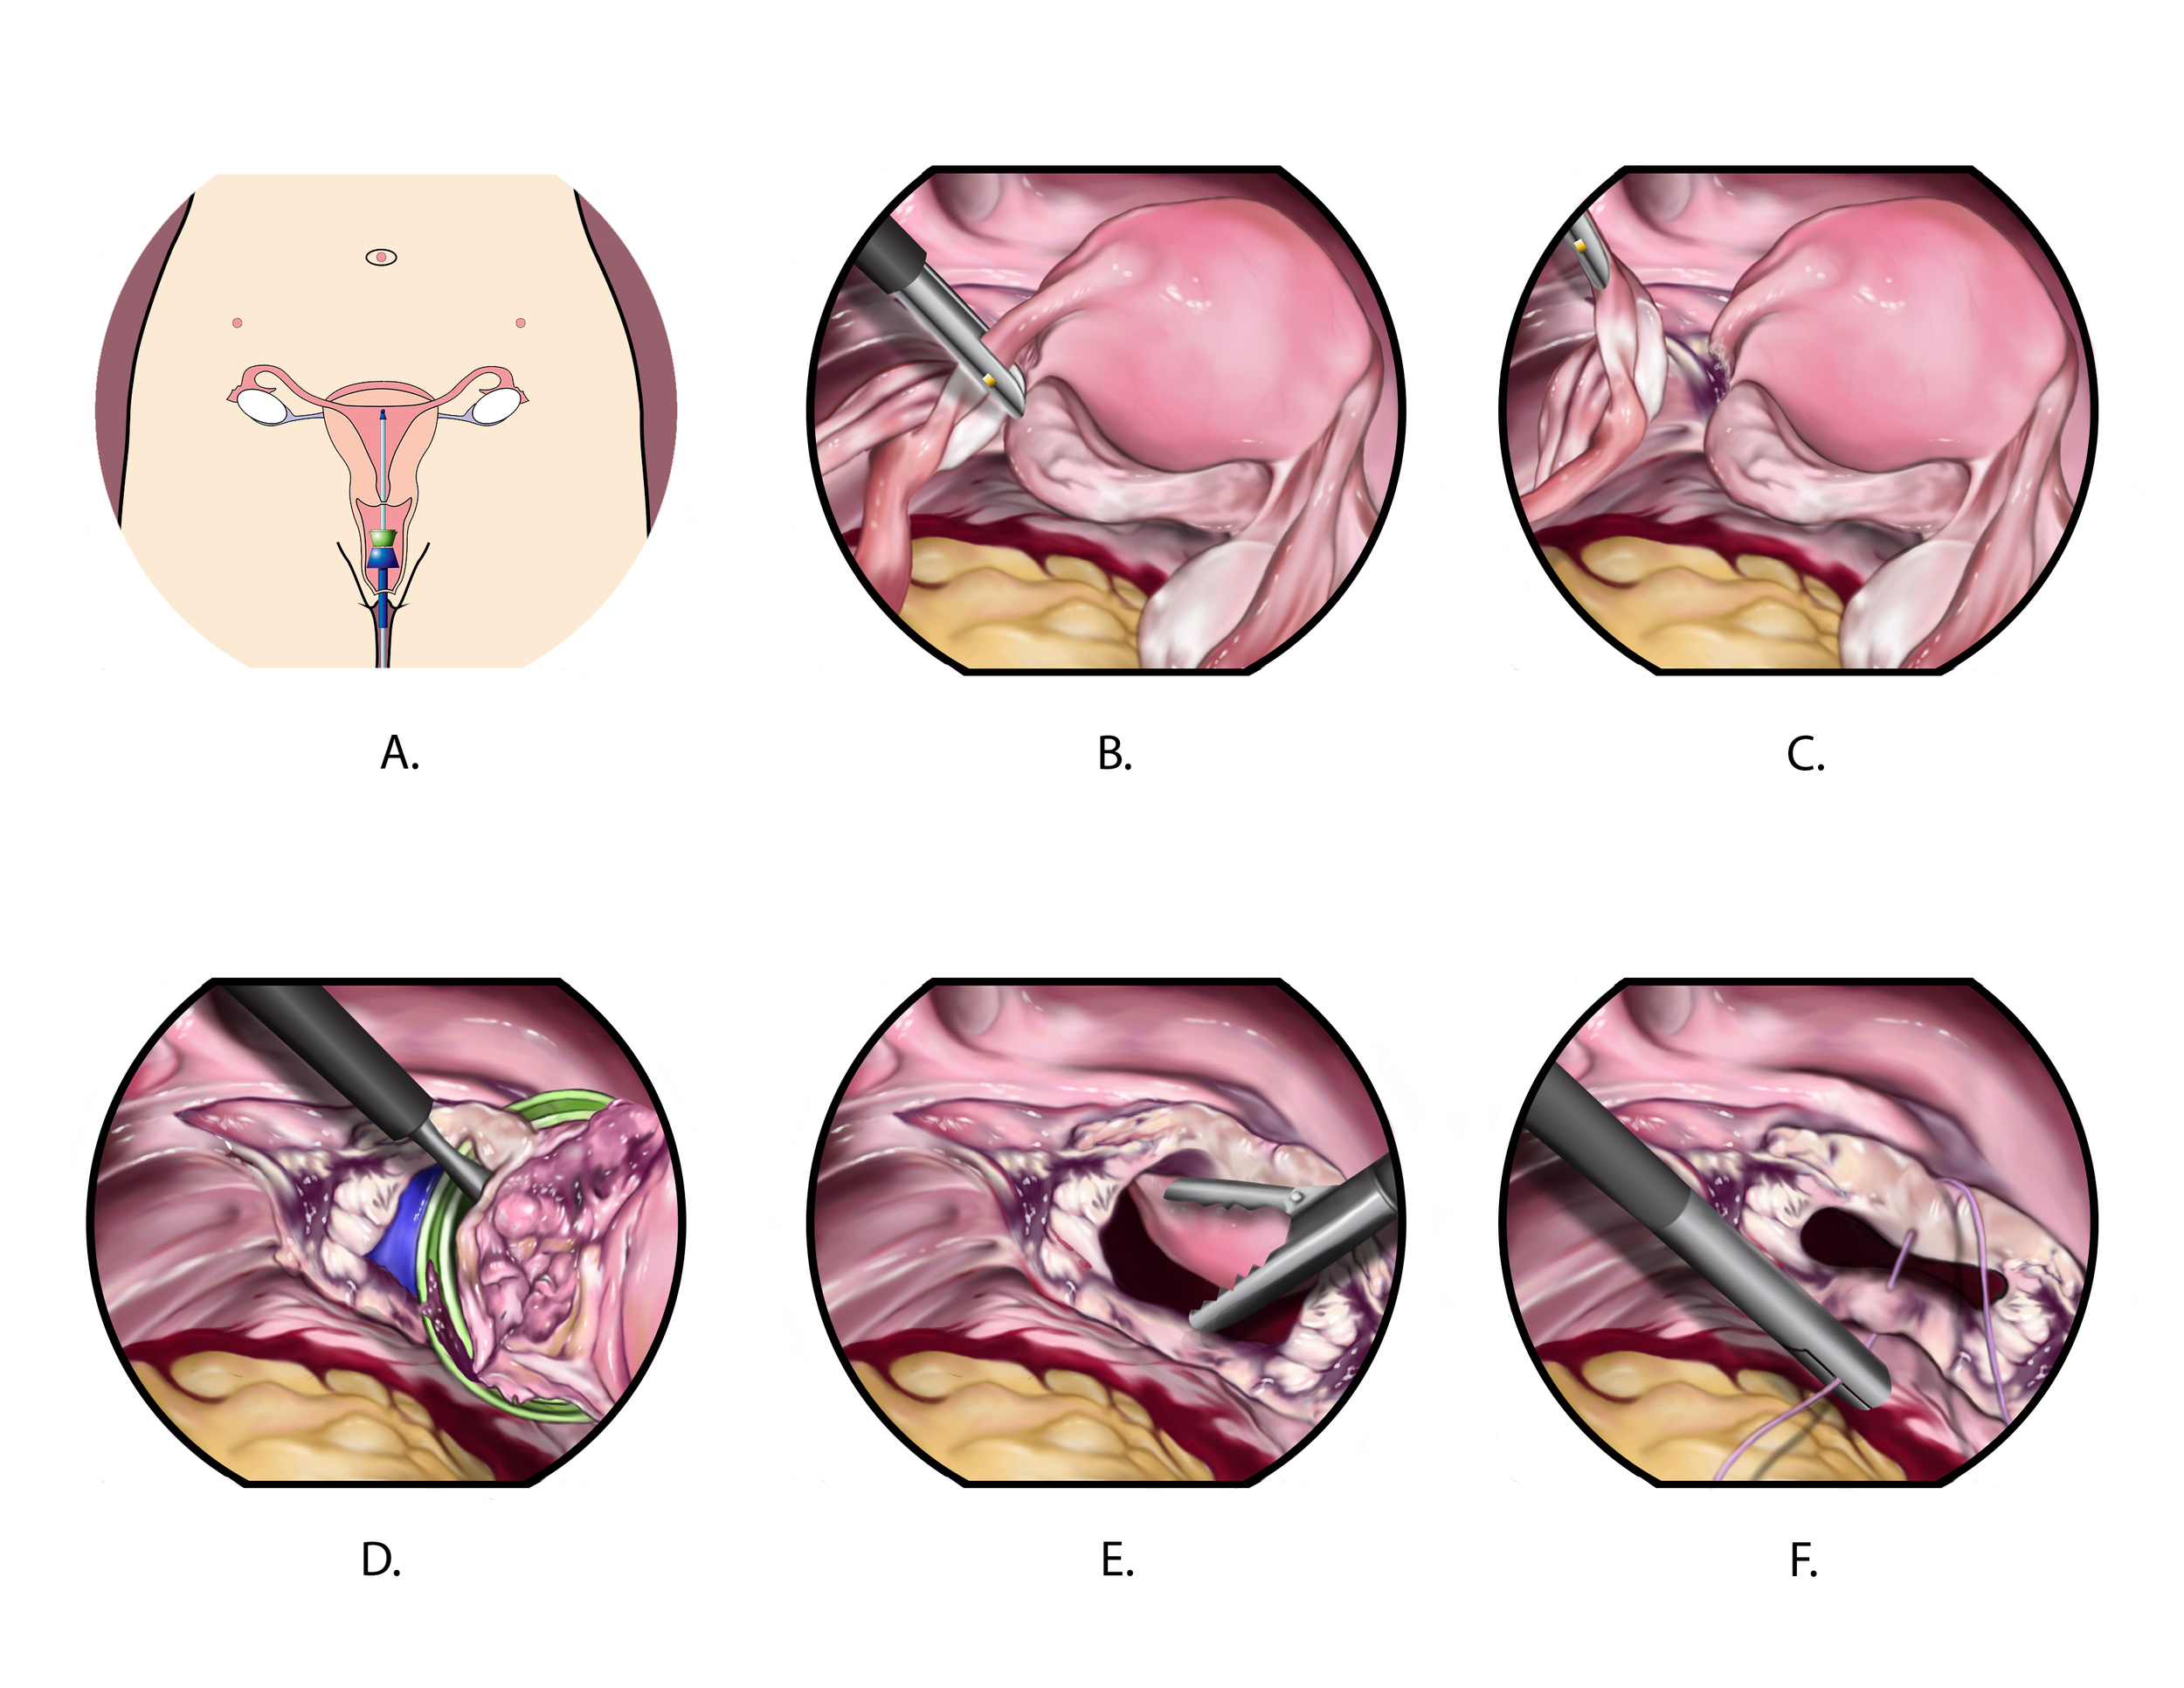

Biomedical art is a form of biological illustration that helps record and disseminate medical, anatomical, and related knowledge. It translates complex technical medical information into visual artwork to support research, patient care and education, public relations, and marketing objectives.